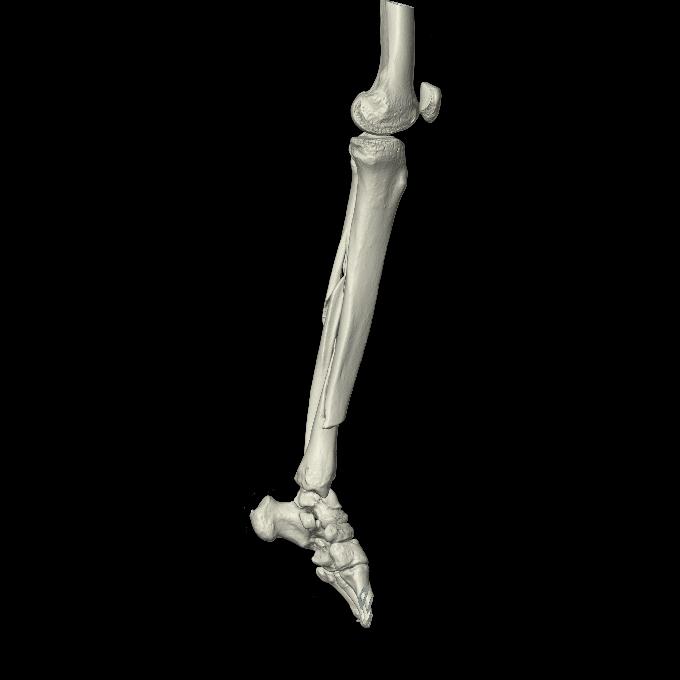

102803 1/12(キウスなし) 1/27 左下腿 4R 30歳女性 左脛骨軸内釘